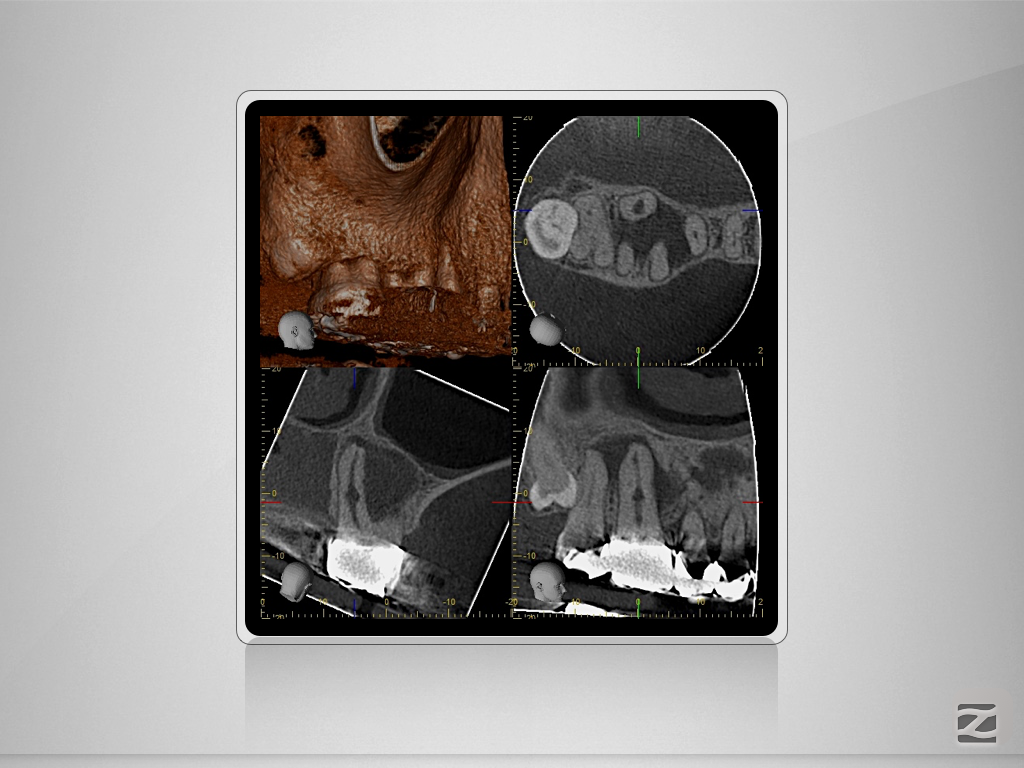

16D.002

Immer schön skeptisch bleiben 4